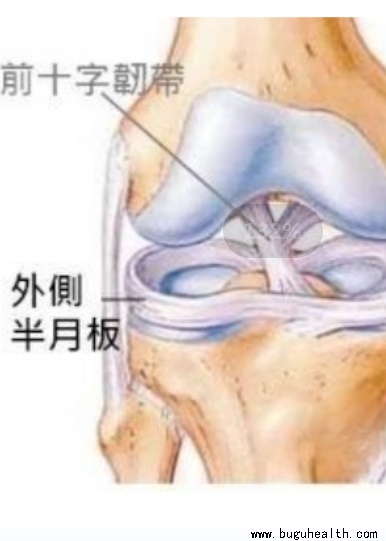

- 半月板(meniscus)是膝关节中的纤维软骨,是保护膝盖防止退化最重要的组织,它可以吸收运动时的震荡,传递下肢的力量,润滑和稳定膝盖关节。 .....

- 半月板损伤,是一种很常见的膝关节损伤,经常会有朋友尤其是那些热爱运动的朋友们,会问到类似的问题,询问自己的半月板损伤到底严不严重,要不要手术,损伤后还能运动吗?今天就带大家了解半月板.....

- 半月板损伤,是指半月板因外伤或退行性病变而出现损伤,是膝关节中最常见的损伤。半月板损伤患者可出现关节疼痛、肿胀、膝关节活动受限、关节交锁、弹响等症状。半月板损伤要采用医疗康复和自我康复结合的方式,一般恢复较慢,时间较长;只要采用恰当的方法,半月板损伤是可以预防的。.....